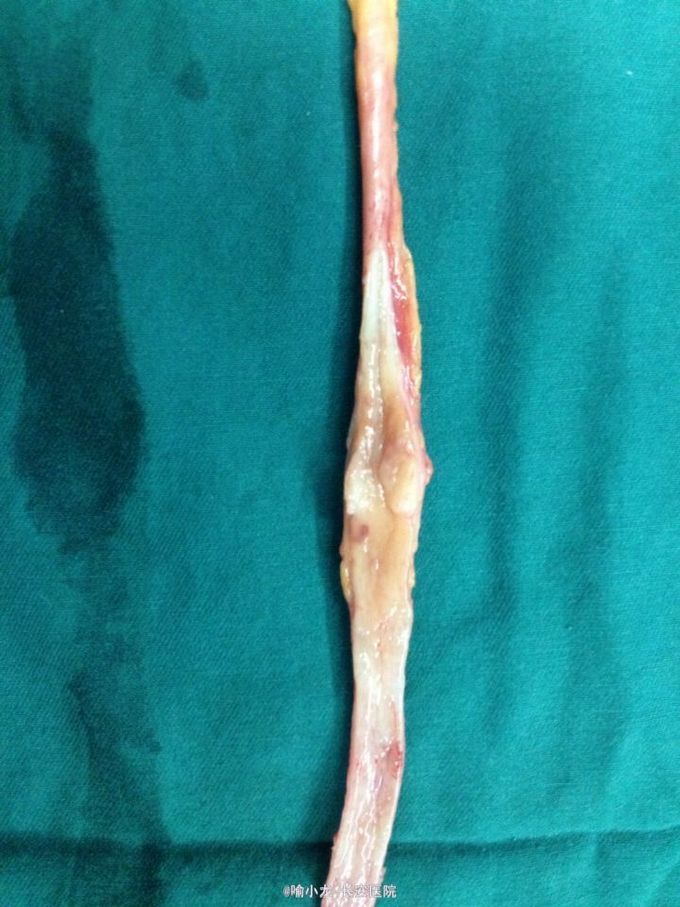

入院查血常规、肝肾功能、电解质、血脂六项、凝血四项、肿瘤四项、粪常规均基本正常;尿液分析示潜血3+,白细胞+;入院留48小时尿培养阴性;血型鉴定B型,血气分析、输血前四项基本正常;心电图、心脏彩超、腹部彩超、胸片及胸部CT检查均大致正常;下腹部+盆腔CT示左侧肾盂伴左侧输尿管全程扩张,右侧肾囊肿大小约2.0cmx1.3cm;泌尿系水成像示右肾囊肿约1.4cm,左侧输尿管上段内见条形低信号影。初步诊断:1.左侧输尿管肿瘤;2.左侧肾盂积水;3.右侧肾囊肿;4.泌尿系感染;5.高血压3级。入院后抗感染、止血对症治疗后,阵发性血尿无缓解,出现左侧肾绞痛伴发热乏力,遂急诊行膀胱镜检查并置入输尿管导管,术后阵法性血尿仍不缓解,2天后在静脉全麻下急诊行膀胱输尿管镜检查+左侧双J管置入术,术后间断寒战发热,最高体温39℃,化验尿培养示大肠埃希氏菌,病检示左输尿管高级别乳头状尿路上皮癌,根据药敏抗感染疗5天后,体温渐恢复并稳定,4天后在全麻下行左侧肾脏输尿管根治性切除术,术后病理示输尿管中段高级别乳头状尿路上皮癌局灶侵及固有层,外膜未见癌侵润,术后恢复良好。